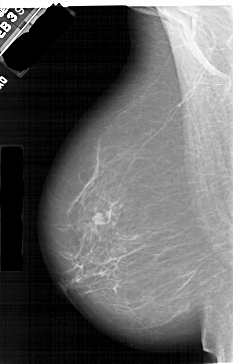

A_1409_1.LEFT_MLO

LEFT_MLO LINES 6541 PIXELS_PER_LINE 4186 BITS_PER_PIXEL 12 RESOLUTION 43.5 NON_OVERLAY